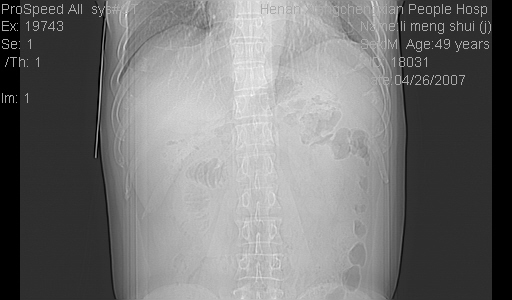

| 患者,男,49岁, 腹疼伴恶心\\呕吐20天,20天前无明显诱因出现右上腹部疼痛,钝疼,无放射,伴恶心\\呕吐,不伴发热.患者不愿增强. b超:肝脏右叶实性占位. ct:肝脏右叶可见一巨块状圆形低密度影,大小约93mm*84mm,其内可见点状高密度影,胆囊、胰腺、脾脏大小、形态及密度未见异常,腹膜后间隙未见肿大淋巴结影。 印象:肝脏右叶巨大肿块,性质待定,建议增强并穿刺活检进一步确诊。 ct平扫: ![]() ![]() ![]() ![]() ![]() ![]() ![]() ![]() ![]() ![]() ![]() ![]() ![]() ![]() ![]() ![]() ![]() 肝脏右叶肿块ct引导下穿刺活检术 患者于16时05分仰卧于ct检查台上,首先行肝脏ct扫描确定进针位置、深度、角度。在局麻下行ct引导下肝脏右叶肿块穿刺活检术。常规消毒、铺巾、局麻。在ct引导下使活检针经右侧腋中线、第9肋间隙垂直胸壁进针90mm,针头进入病变预定位置。在病变预定位置多点、多方向抽取小米样病变组织多块,涂片五张送病理检查。术后穿刺点局部无出血,未出现腹腔积液等并发症。术中及术后患者生命体征稳定,手术于17时10分成功完成。患者安返病房。 穿刺片 ![]() ![]() ![]() ![]() ![]() ![]() ![]() ![]() ![]() ![]() ![]() ![]() ![]() ![]() ![]() ![]() 病理结果肝细胞癌 ![]() 原贴地址:http://www.radinet.com.cn/forum_view.asp?forum_id=4&view_id=24130 ok |